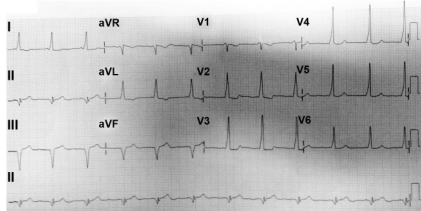

Na doença demonstrada no eletrocardiograma abaixo, observamos que: